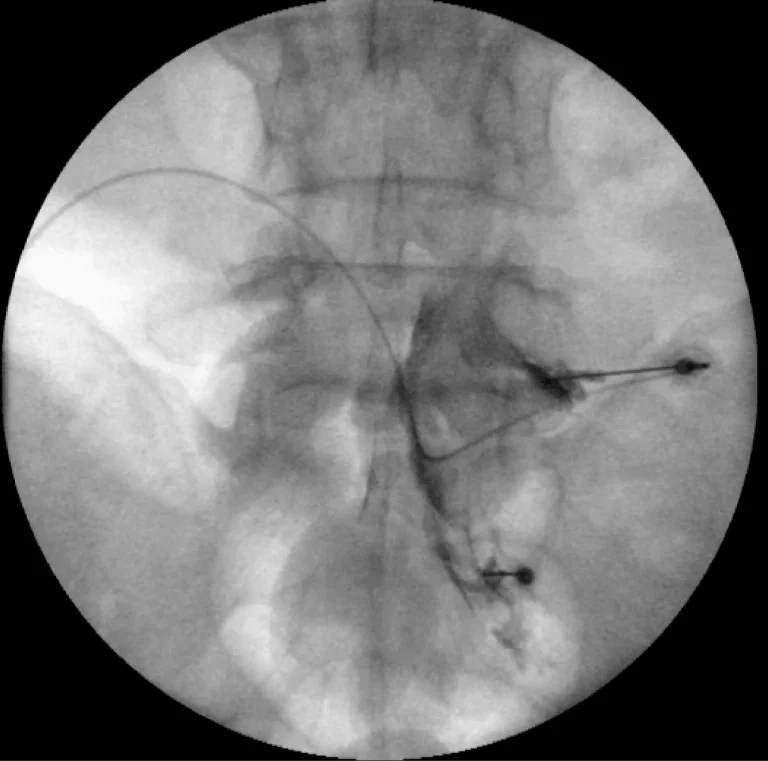

X-ray image showing a catheter inserted into blood vessels.

Step 1: X-Ray Guidance

Fluoroscopic (X-ray) guidance is used to visualize the spine and guide needle placement in real time.